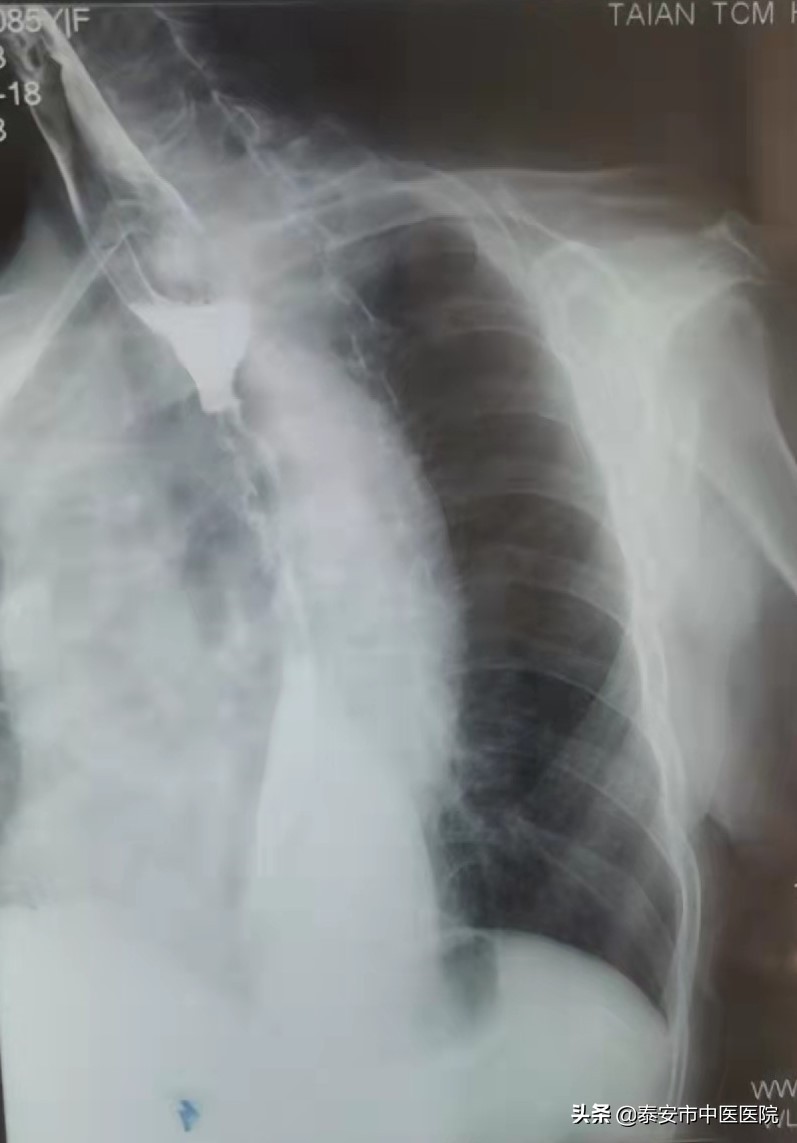

消融前食管钡餐